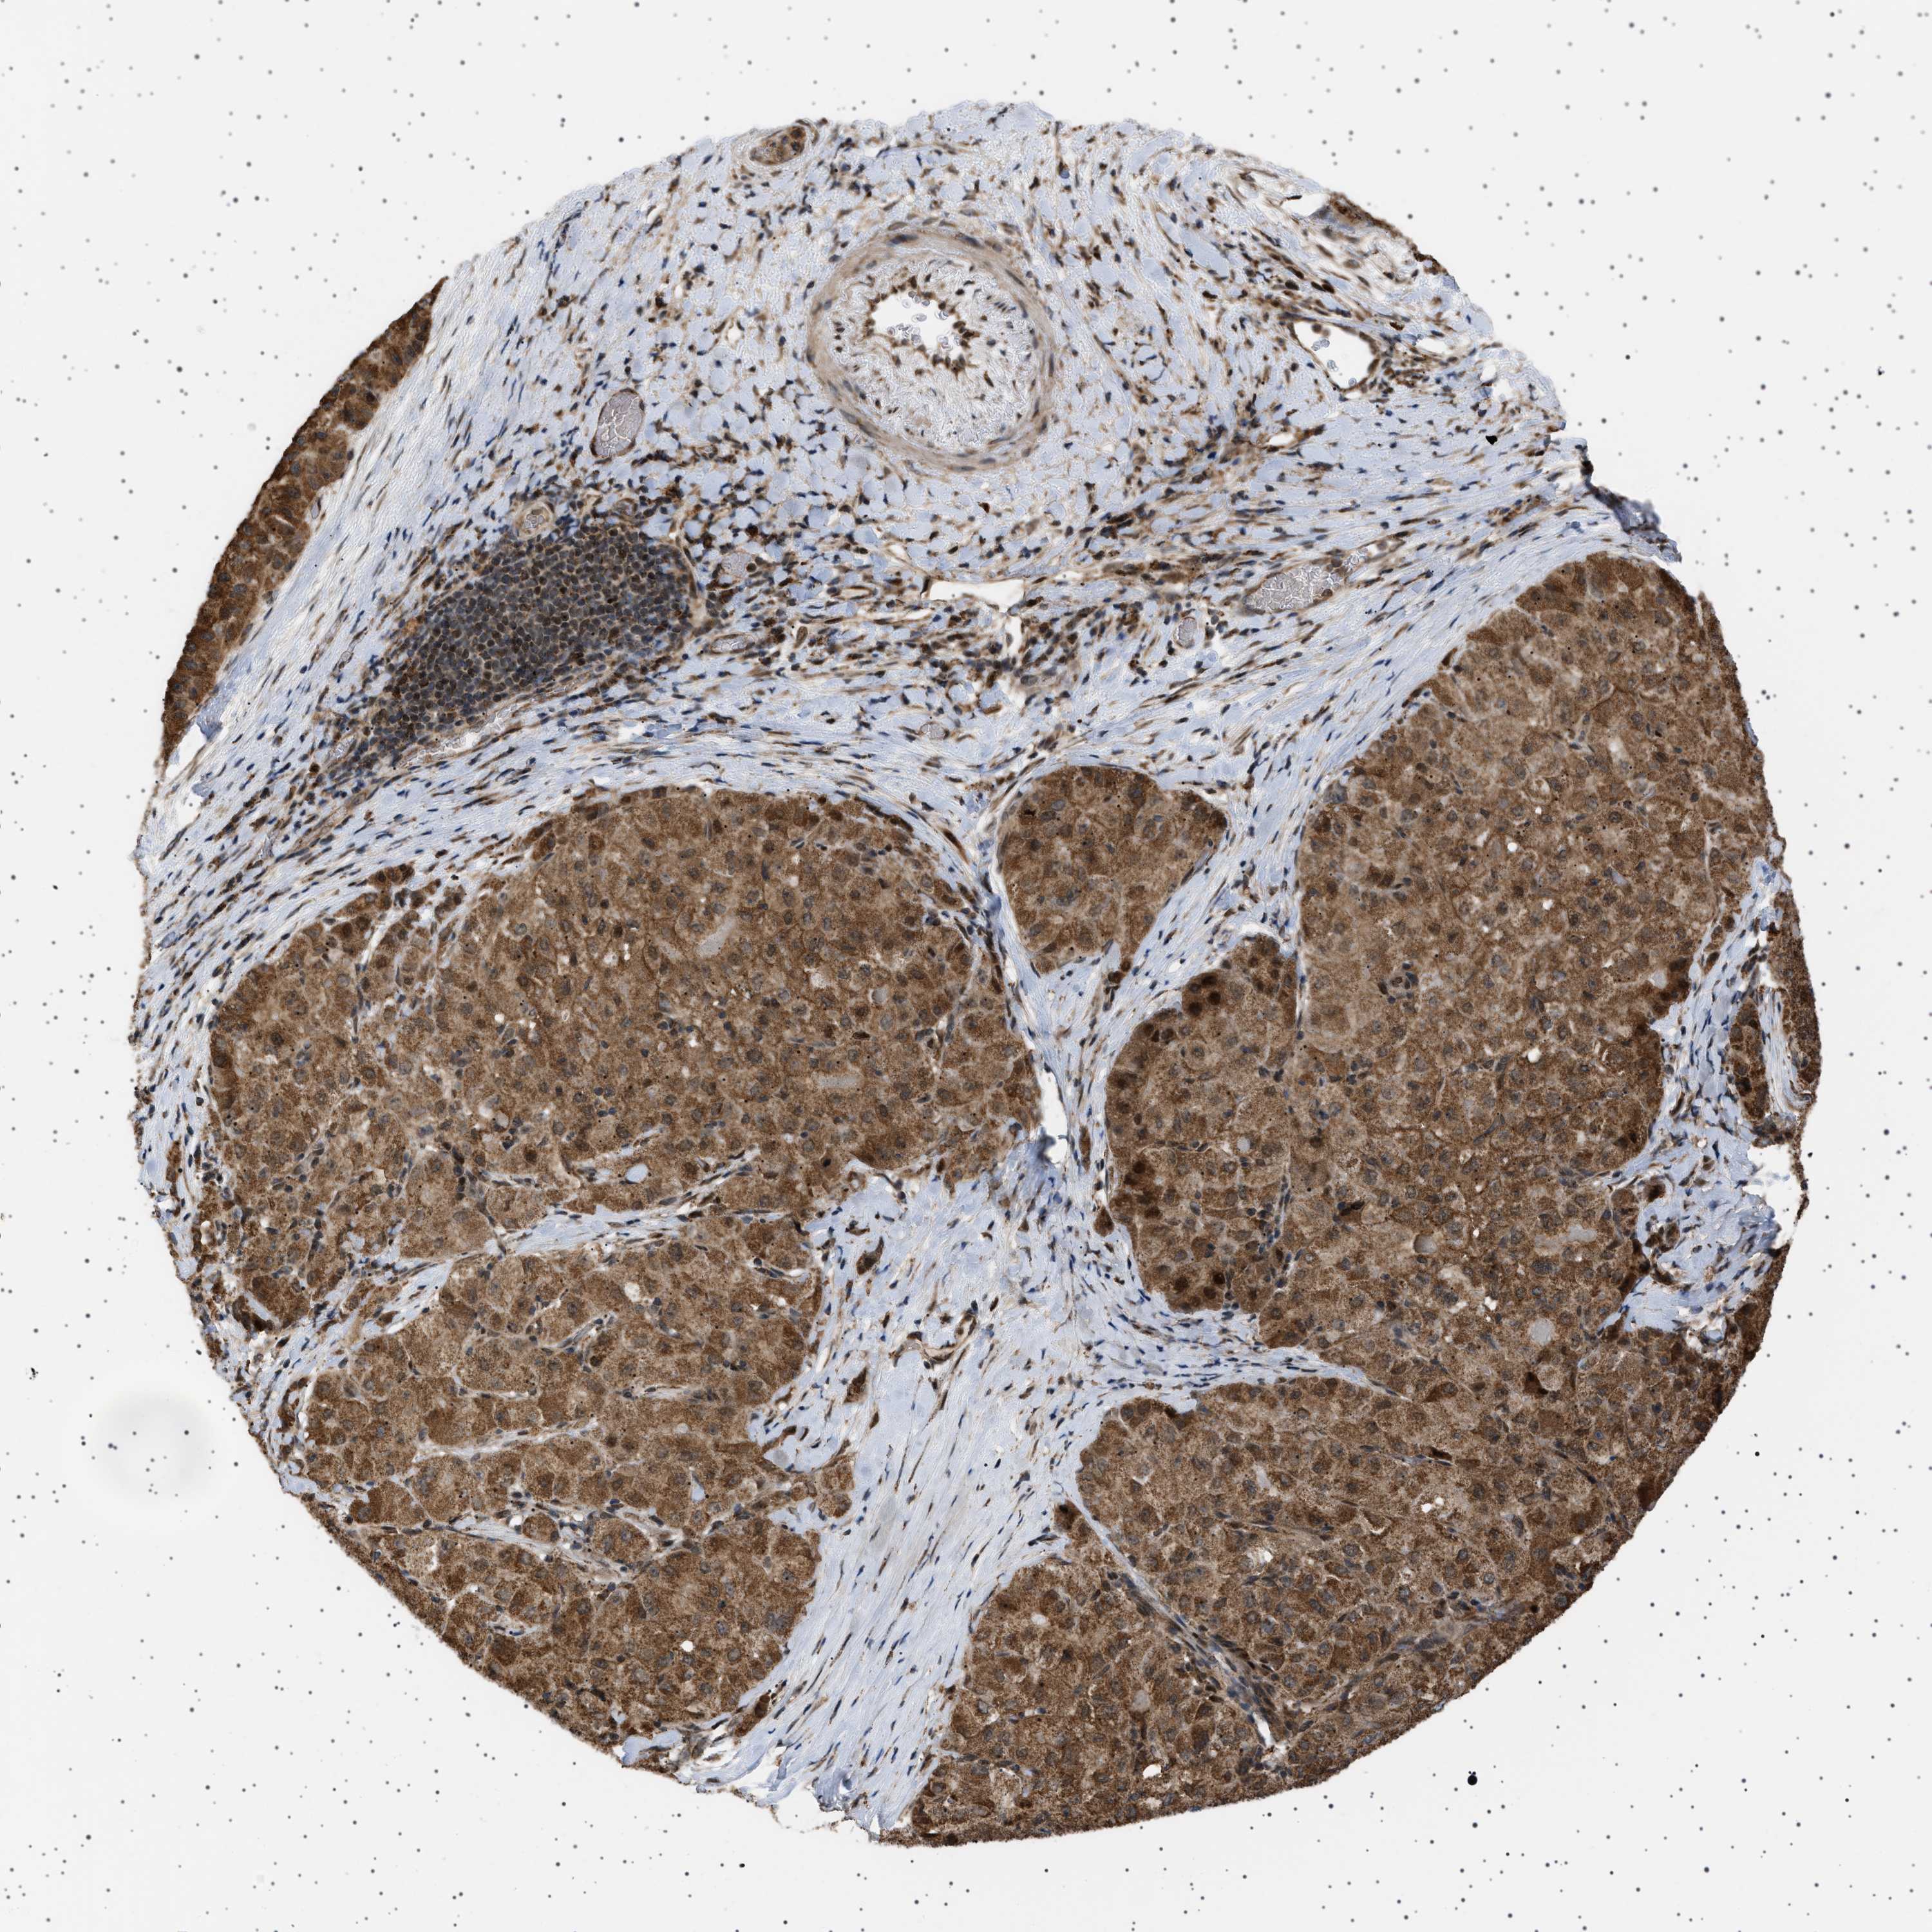

LIVER CANCER - Protein expressioni

A mouse-over function shows sample information and annotation data. Click on an image to view it in a full screen mode. Samples can be filtered based on level of antibody staining by selecting one or several of the following categories: high, medium, low and not detected. The assay and annotation is described here.

Note that samples used for immunohistochemistry by the Human Protein Atlas do not correspond to samples in the TCGA dataset.

Antibody stainingi

Antibody staining in the annotated cell types in the current human tissue is reported as not detected, low, medium, or high, based on conventional immunohistochemistry profiling in selected tissues. This score is based on the combination of the staining intensity and fraction of stained cells.

Each image is clickable and will lead to virtual microscopy that enables deeper exploration of all samples and also displays staining intensity scores, fraction scores and subcellular localization as well as patient and tissue information for each sample.

Antibody HPA017214

Staining

High

Medium

Low

Not detected

Intensity

Strong

Moderate

Weak

Negative

Quantity

>75%

75%-25%

<25%

None

Location

Nuclear

Cytoplasmic/membranous

Cytoplasmic/membranous,nuclear

Cholangiocarcinoma

Carcinoma, Hepatocellular, NOS